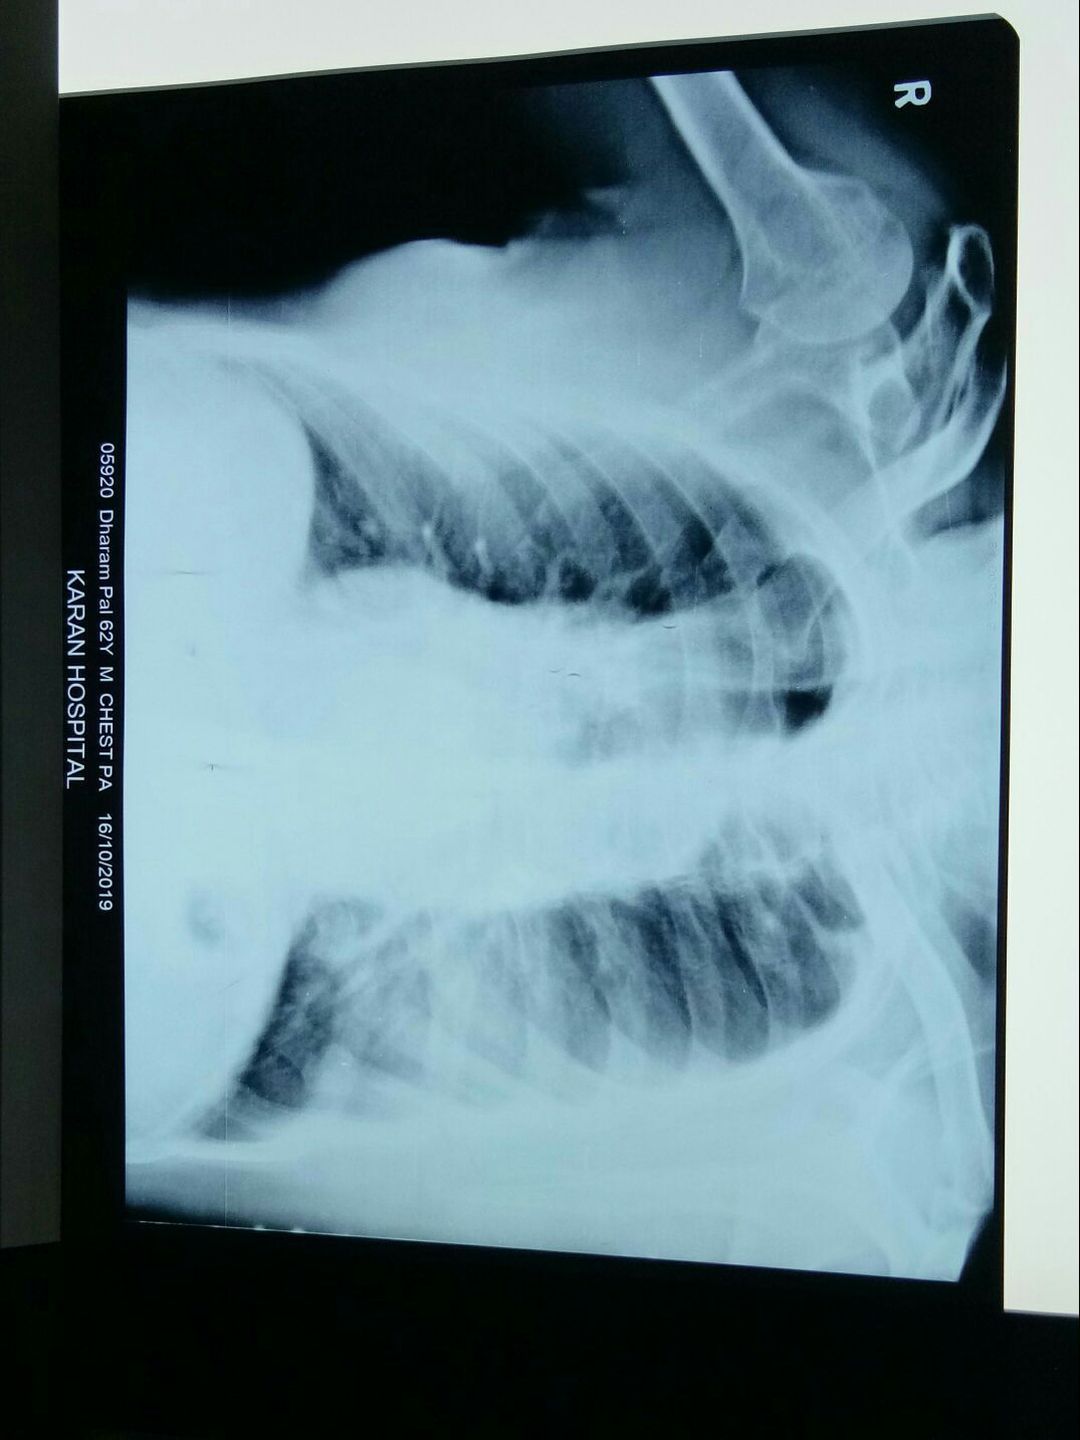

Radiology

Pulmonology

Pneumonia

Large